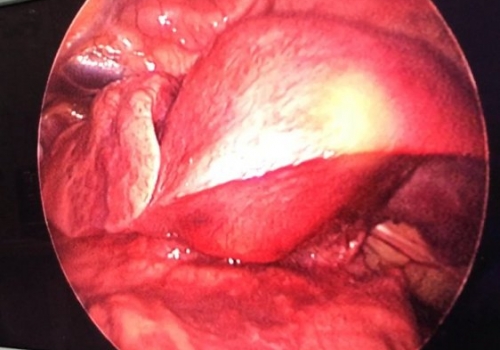

MediastinalTeratoma .Torokoskopik teratomanın eksiziyası

Daha bir çətin əməliyyat 8 yaşlı pasientdə döş boşluğunda törəmə- Ağciyərin orta payı üzərində böyük həcmli törəmə Teratoma. Torokoskopik törəmənin eksiziyası

Dr. Toğrul Ömərov